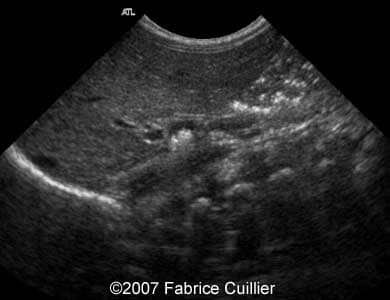

A 30-year-old patient, G3P2, was referred to our clinic at 36 weeks of gestational age after hyperechoic foci were seen in the fetal gallbladder on ultrasound. 13- and 22-week sonographic examinations were unremarkable. The 36-week ultrasound evaluation was normal except for an elongated echogenic mass seen in the gallbladder (Images 1A, 1B, 1C, 1D). Neither ascites nor hydrops were seen. The gallbladder appearance was identical on sonographic re-evaluation at 37 weeks GA (Images 3A, 3B). At 38 weeks of gestational age, a healthy female infant weighing 3200 g was born. There was no evidence of hematologic incompatibility, sepsis, or jaundice. Laboratory values including those for the cystic fibrosis gene, hemoglobinopathy, and liver functions were normal. On the fifth day of life, ultrasound was performed, showing a gallbladder of normal size containing several gallstones (Images 5A, 5B, 5C, 5D).

Images 3A, 3B. Sonogram obtained at 38 weeks of gestational age showing multiple small echogenic foci in the fetal gallbladder.

3A

3B